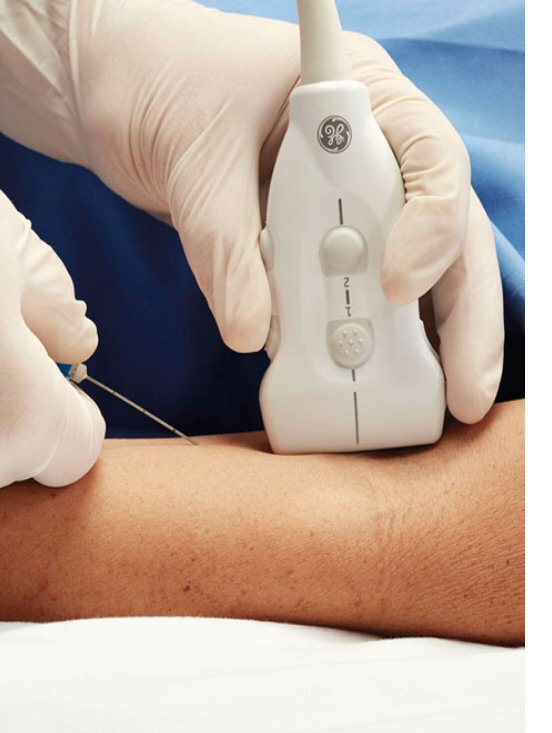

Η παρακέντηση ογκιδίων με καθοδήγηση υπερήχων αποτελεί μια εύκολη, γρήγορη και ασφαλή εξέταση καλά ανεκτή από τους ασθενείς.

Τρόπος εκτέλεσης της εξέτασης:

Ο Ιατρός – Ακτινολόγος μελετά την περιοχή ενδιαφέροντος με υπέρηχο π.χ θυρεοειδής και εντοπίζει την πιο ύποπτη περιοχή.

Ο Ιατρός – Ακτινολόγος εισάγει στο σημείο αυτό βελόνα αιμοληψίας, της οποίας η πορεία παρακολουθείται υπερηχογραφικά ώσπου η άκρη της να εισέλθει στο ογκίδιο το οποίο χρήζει βιοψίας, αποφεύγοντας έτσι την τρώση παρακείμενων δομών ή αγγείων.

Στην συνέχεια αναρροφάται υλικό και αποστέλλεται για κυτταρολογικό έλεγχο. Τα αποτελέσματα του FNA (βιοψία) αποστέλλονται στον εξεταζόμενο σε 48ώρες.

Η μέθοδος δεν χρειάζεται καμία προετοιμασία πλην της αποφυγής λήψης ασπιρίνης ή αντιπηκτικών (όπου δύναται), καθώς υπάρχει η πιθανότητα να δημιουργηθεί αιμάτωμα στο σημείο της παρακέντησης.

Δεν υπάρχει κανένας περιορισμός μετά το τέλος της εξέτασης.

Η παρακεντήσεις ογκιδίων με καθοδήγηση υπερήχων αποτελούν μια εύκολη, γρήγορη και ασφαλή εξέταση καλά ανεκτή από τους ασθενείς.

Τρόπος εκτέλεσης της εξέτασης:

Ο Ιατρός – Ακτινολόγος μελετά την περιοχή ενδιαφέροντος με υπέρηχο π.χ θυρεοειδής και εντοπίζει την πιο ύποπτη περιοχή.

Ο Ιατρός – Ακτινολόγος εισάγει στο σημείο αυτό βελόνα αιμοληψίας, της οποίας η πορεία παρακολουθείται υπερηχογραφικά ώσπου η άκρη της να εισέλθει στο ογκίδιο το οποίο χρήζει βιοψίας, αποφεύγοντας έτσι την τρώση παρακείμενων δομών ή αγγείων.

Στην συνέχεια αναρροφάται υλικό και αποστέλλεται για κυτταρολογικό έλεγχο.

Τα αποτελέσματα του FNA (βιοψία) αποστέλλονται στον εξεταζόμενο σε 48ώρες.

Η μέθοδος δεν χρειάζεται καμία προετοιμασία πλην της αποφυγής λήψης ασπιρίνης ή αντιπηκτικών (όπου δύναται), καθώς υπάρχει η πιθανότητα να δημιουργηθεί αιμάτωμα στο σημείο της παρακέντησης.

Δεν υπάρχει κανένας περιορισμός μετά το τέλος της εξέτασης.